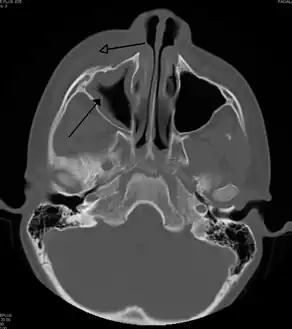

Maxillary sinusitis caused by a dental infection associated with periorbital cellulitis

Sinus infection can spread through anastomosing veins or by direct extension to close structures. Orbital complications were categorized by Chandler et al. into five stages according to their severity (see table).[26] Contiguous spread to the orbit may result in periorbital cellulitis, subperiosteal abscess, orbital cellulitis, and abscess. Orbital cellulitis can complicate acute ethmoiditis if anterior and posterior ethmoidal veins thrombophlebitis enables the spread of the infection to the lateral or orbital side of the ethmoid labyrinth. Sinusitis may extend to the central nervous system, where it may cause cavernous sinus thrombosis, retrograde meningitis, and epidural, subdural, and brain abscesses.[27] Orbital symptoms frequently precede intracranial spread of the infection . Other complications include sinobronchitis, maxillary osteomyelitis, and frontal bone osteomyelitis.[28][29][30][31] Osteomyelitis of the frontal bone often originates from a spreading thrombophlebitis. A periostitis of the frontal sinus causes an osteitis and a periostitis of the outer membrane, which produces a tender, puffy swelling of the forehead.

Infection of the eye socket is a rare complication of ethmoid sinusitis, which may result in the loss of sight and is accompanied by fever and severe illness. Another possible complication is the infection of the bones (osteomyelitis) of the forehead and other facial bones – Pott's puffy tumor.[16]